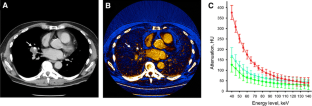

Fig. 2